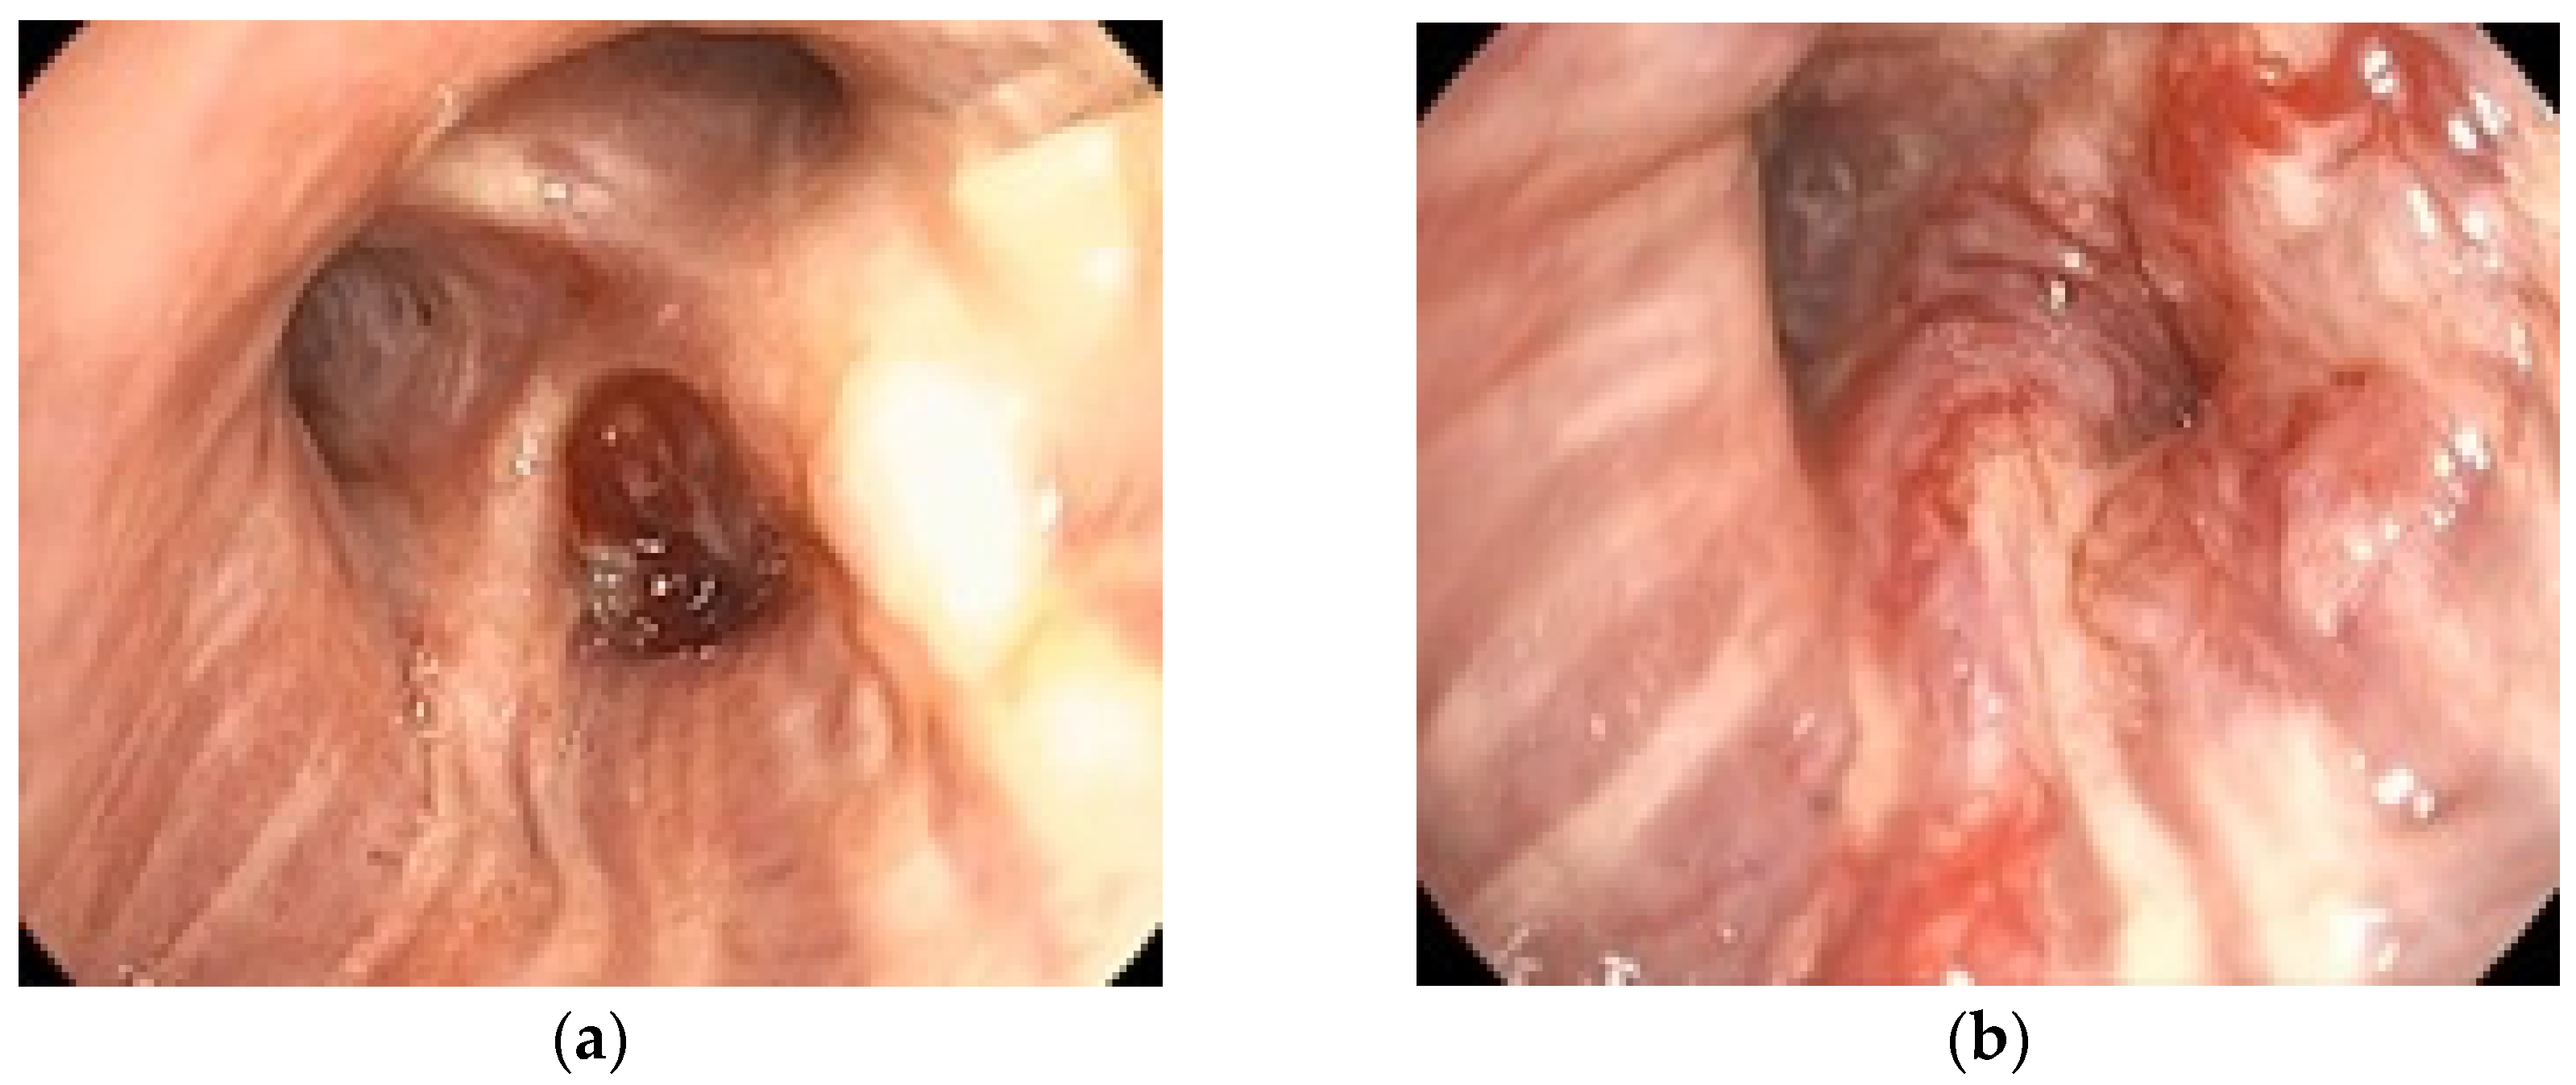

To illustrate the clinical relevance of early endoscopic evaluation, Figure 2 shows the rapid progression of a case of bronchial adenocarcinoma with notable changes occurring within one month. The tumor diameter increased from 28 mm in December 2023 to 45 mm in January 2024, over a one-month interval without oncologic treatment. These quantitative measurements highlight the aggressive nature of the disease and the importance of timely staging. This example supports the need for accurate staging, achievable by bronchoscopy and EBUS.

Figure 2. Adenocarcinoma of the dorsal segment of the right upper lobe in a 72-year-old male ex-smoker, well vascularized, with distal invasion of the lobar bronchus and significant stenosis of its segmental branches due to extrinsic compression and mucosal infiltration. Rapid growth in one month with lack of any oncologic treatment: (a) 12 December 2023; (b) 16 January 2024.